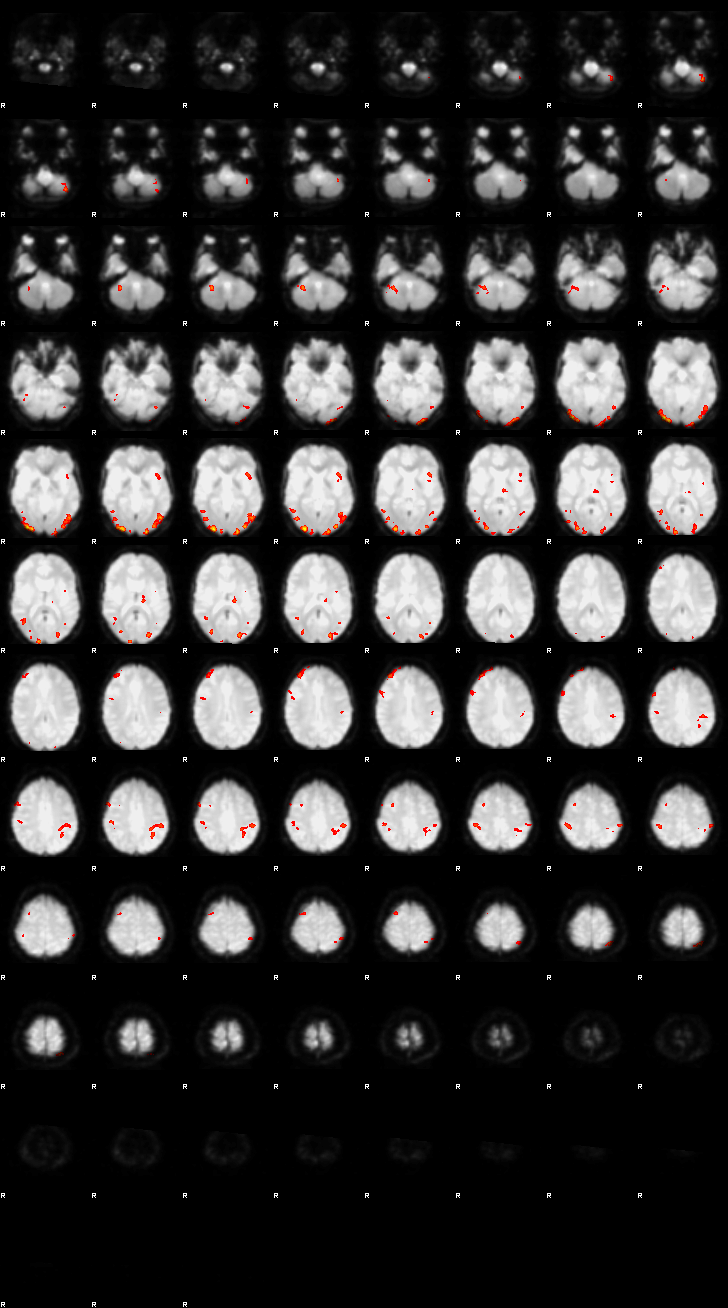

Visualization of First-level Design and Results (Run 1)#

Below, the design matrix and selected results from the first run are shown. Since both runs use the same design and contrasts, the results of the second run can be explored using the same approach.

Let’s now display the thresholded activation maps. A voxelwise threshold of Z > 3.1 was applied, followed by cluster-level correction at p < 0.05 (corrected for multiple comparisons).

zstat1 - C1 (incongruent)

zstat2 - C2 (congruent)

zstat3 - C3 (incongruent-congruent)

display(Markdown("#### Incongruent"), rendered_thresh_zstats1)

Incongruent

display(Markdown("#### Congruent"), rendered_thresh_zstats2)

Congruent

display(Markdown("#### Incongruent-Congruent"), rendered_thresh_zstats3)

Incongruent-Congruent